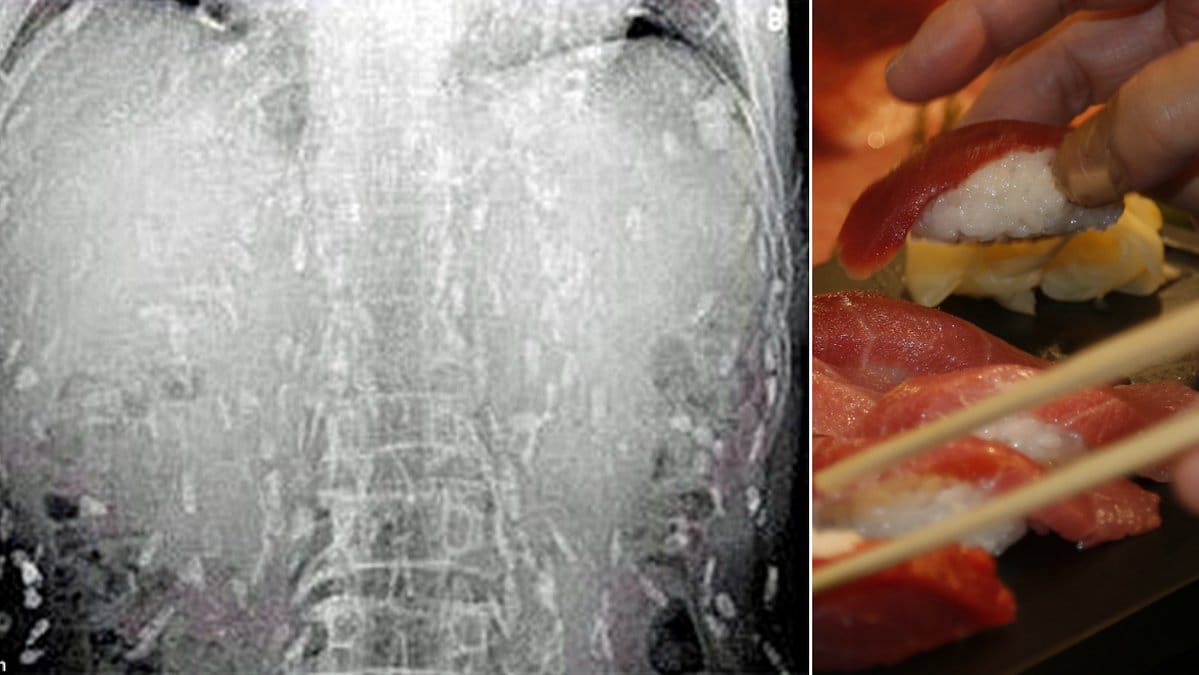

GUANGZHOU. Sashimi är det bästa med sushi. Förutsatt att det inte är dålig fisk, då. Är det så kan det nämligen gå som för en kinesisk man. Han gick nämligen till läkaren med magont och kliande hud – och fick beskedet att hela hans kropp var full av bandmaskar, skriver Daily Mail.

Ännu värre blir det för oss älskare av rå fisk eftersom att det enligt läkarna antagligen beror på att mannen åt alldeles för mycket – rå fisk. Dålig rå fisk, alltså.

Alla sushiälskare kan pusta ut. Det har visat sig att nyheten om fiskmaskarna, som spreds av flera svenska och internationella medier faktiskt var falsk. Enligt Metro har röntgenbilderna använts flera gånger, och att dessa parasiter i själva verket kommer från grisar.